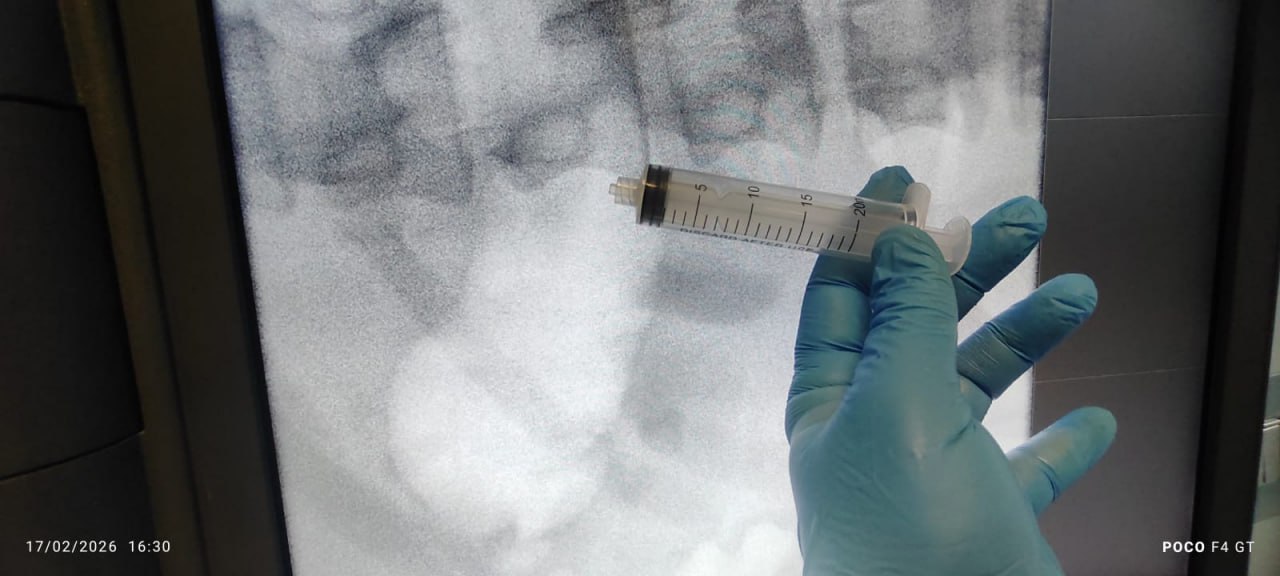

في الجانب الثاني يقف الجراح المتمرس والحاذق المتخصص بأمراض المسالك البولية والكلى الدكتور"منتظر جمال الطرفي" مع فريقه الطبي ليحقق الانجاز تلو الانجاز ويصف حالة المريض لوكالة نون الخبرية قائلا ان" حالة الشاب "عبد الله" من الناصرية كانت طارئة وادخلت الى صالة العمليات بعد منتصف ليلة الاثنين وانتهت فجر يوم الثلاثاء الماضي، وعنده انسداد في الحالبين حيث توجد حصاة سمكها (3) سنتيمتر في الحالب الايسر، وحصاة اخرى كبيرة في الحالب الايمن سمكها (25× 17) مليمتر، وعنده مشاكل في وظائف الكلى، وقمنا بتفتيت الحصى في الجانب الايسر بواسطة اشعة الليزر والناظور، بدون اي فتحة جراحية في بطنه، بينما ابلغوه في ذي قار انه يحتاج الى عملية جراحية لرفع الكلى، اما في الحالب الايمن فحجم الحصى كبير جدا لا يمكن ازالته بنفس الطريقة، ونوع الحصى هي السيستين وتنبعث منها رائحة الكبريت ( وتسمى (Cystine stones وهي نوع نادر من حصوات الكلى الناتجة عن اضطراب وراثي يسمى "بيلة السيستين"، مما يؤدي إلى تراكم حمض السيستين الأميني في البول وتشكيل بلورات صلبة، وتمثل أقل من (1) بالمئة من حصى الكلى، وتتميز بأنها كبيرة الحجم، تتكون في سن مبكرة(".

واضاف "الطرفي" ان" تلك الحصاة صلدة ويصعب تكسيرها، وقمت بتكسير حوالي (70) بالمئة منها، وتكون على محيطها الالتهابات والجراحة ووضعت لها قسطرتين من جانبين وتمكنت من اخراجها من الحالب"، مبينا ان انسداد الحالبين كان يشكل مشكلة عويصة على المريض لان الانسان العادي يخرج منه الادرار بكمية (2000 ــ 2500 cc)، بينما كانت كمية الادرار تخرج منه خلال ساعة (200 cc) فقط، وبعد اخرج الحصى خرجت منه خلال سبع ساعات (4000 cc) وقمنا بتعويضه بالسوائل حتى لا تحصل لديه تغييرات نتيجة هبوط او ارتفاع الصوديوم والالكترونات والبوتاسيوم، وتكللت عمليته بالنجاح دون ان ترفع كليته وهو الآن في مرحلة التعافي الكامل ولديه كليتين تعملان بشكل جيد".